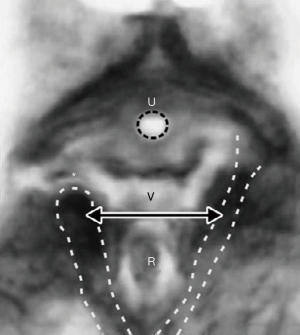

With reference to Figure 10, at “3” the head (circle) can overstretch uterosacral (USL) ligaments to cause uterine prolapse and enterocele. If the lateral ligamentous attachments of the USL to the rectum “R” pull the anterior rectal wall forwards as USLs lengthen, the anterior rectal wall may be stretched forwards to cause rectal intussusception (11) (Figure 11), which can be cured by USL repair (12); at circle “2”, the CL elongation or rupture may cause cystocele’(transverse defect); at circle “4”, perineal damage may cause rectocele and descending perineal syndrome; at circle “1”, excess pressure on the levator muscles may dislocate or tear their collagenous insertions to symphysis pubis, while excess pressure on PUL may cause stress incontinence.

How uterine prolapse may cause anterior rectal intussusception

Examination of Figure 11 indicates how the attachment of USLs to the lateral wall of the rectum can cause intussusception in women who have uterine prolapse. As USLs lengthen, they splay laterally, causing the anterior rectal wall to also elongate laterally; such stretching weakens the rectal wall structurally. Its collagen concentration lessens and the anterior rectal wall invaginates to cause intussusception (11).